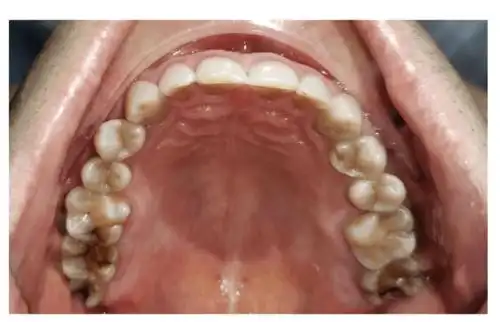

乳牙列的上颌:10颗牙恒牙列的上颌:14颗牙(除外智齿)而拔牙矫治后剩余